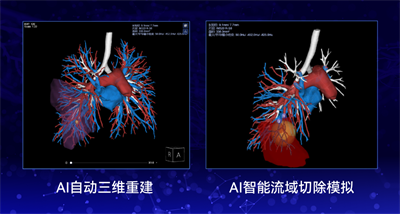

为达成这个目标,基于影像检查的高精度三维重建和个性化手术方案的制定必不可少。然而,传统的三维重建需要大量的人工交互操作、繁杂耗时,给医生带来了沉重的工作负担、限制了能够精细重建的病例数量,同时在脉管等精细结构的重建效果上也存在一定的局限性。

基于先进的人工智能算法以及丰富的医学图像三维重建技术,商汤科技SenseCare® Lung Surgical Planning肺部智能手术规划系统为精细化和个性化肺癌手术方案的确定提供了新范式。系统可实现全自动的胸部多种组织结构的精细分割与三维重建,重建时间由传统医生手工操作的2-4小时大幅缩短至2-5分钟,并提供针对多种术式方案的360°实时交互模拟分析,结果立等可取,可以有效辅助医生进行个性化精准术前模拟与术后评估。

通过提取及重建胸部CT影像,系统可对胸部组织结构、脉管分布、病灶等进行三维智能交互式查看,方便医生进行更全面精准的术前评估。尤其是针对微小磨玻璃结节等术中较难定位的疑难病例,医生可以借助系统根据血管、气管的走形以及与病灶的相对位置进行小病灶的定位,帮助胸外科医生在术中也能精准找到结节。

同时,系统还能够通过肺段甚至亚段级别的切除模拟,帮助医生进行更精细化的切除手术设计,更多地保留肺组织,提高术后生存质量和预后效果,真正做到个体化、精准化治疗。

基于此,该院引入SenseCare®Lung Surgical Planning肺部智能手术规划系统,在胸外科、手术室内等不同场景下都可以灵活使用三维手术规划,同时通过流域术式切除功能来模拟夹断血管后影响的肺部切除范围,并量化术后剩余肺功能组织体积,帮助该院胸外医生针对大量复杂案例实现高效精准的手术规划。

为了在保证手术成功率、尽量保留患者的健康肺组织,该院医生借助SenseCare®Lung Surgical Planning肺部智能手术规划系统重建了肺部组织,用户可以交互式隐藏非手术区域,专注查看病灶周围的组织和脉管结构,可以通过病灶外扩的功能查看该手术切除目标区域的责任血管,并通过精细化流域切除功能实现右下肺前基底亚段切除规划与模拟。